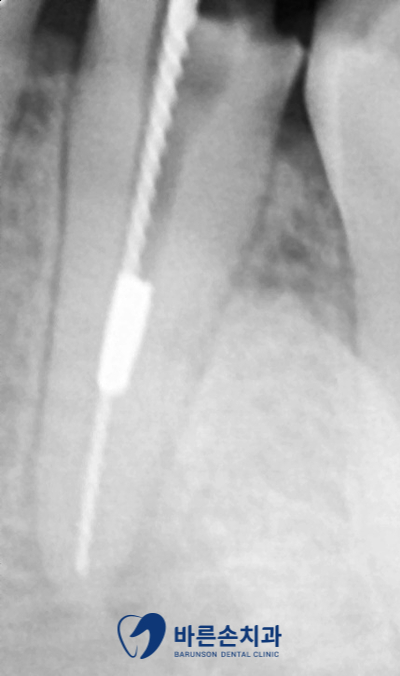

안녕하세요. 의정부 <바른손 치과>입니다. 오늘은 재신경치료에 대해서 설명드리겠습니다! 신경치료 한 치아에 염증이 발생됐다며 오신 환자분입니다. 파노라마 사진 상에 화살표 부분 보시면! 치아 뿌리 끝에 둥글게 까만색 원이 보이시나요?? 이미 신경 치료가 된 치아인데 염증이 생겼습니다… 통증도 있다고 하셨어요.. 자세히 보니 끝까지 신경치료가 완벽히 된게 아니였습니다. 그렇기 때문에 다시 한번 치아를 살려보자! 해서 재 신경치료를 진행했습니다. 먼저 치아 안에 충전되어있던 재료를 다 제거하고 다시 깨끗한 상태로 만듭니다. 염증도 엄청 많으셨고 발치 가능성도 있다고 설명드렸습니다. 신경관 안에 흰색 금속 무언가가 보였는데요. 제거는 되지 않았지만, 막힌 신경관을 확보하여 기구가 신경관 끝까지 들어가기 때문에 신경치료에는 문제가 되지 않았습니다! 수차례 소독과 배농 후 통증이 사라지셔서 신경관을 GP 콘 이라는 재료로 뿌리끝까지 채웠습니다. 남아있는 치아 머리 부분이 얼마 없기에 기둥(포스트)이 필요하셨고 레진으로 치아 벽도 만들었습니다. 크라운 제작을 위해 본을 뜨고 임시치아도 만들어드린 후 보철물이 제작될 때까지 일주일 정도 시간이 필요했어요. 이렇게 크라운도 씌우고 재신경치료를 마무리했습니다!! 앞으로 아무 통증 없이 잘 쓰셨으면 좋겠네요^^ 신경치료 후 염증이 생긴다고 해서 다 발치로 이어지지는 않습니다. 3D CT 촬영을 통해, 진단 후 재신경치료로 다시 살리는 경우가 많거든요!! 특히 오늘 알아본 케이스와 같이, 앞니의 경우에는 간단히 끝나는 경우도 많습니다!^^ 이렇게 재신경치료에 대해 보셨는데요! 다른 게시글에도 재신경치료의 내용이 있으니 참고해주세요~ 감사합니다^^ #의정부바른손치과 #신곡동바른손치과 #의정부치과추천 #의정부신경치료 #의정부보철치료 #의정부크라운 #의정부인레이 #의정부충치치료 #의정부치아교정 #의정부치아미백 #의정부원데이미백 #의정부임플란트 #의정부턱관절 #신곡동임플란트 #금오동임플란트 #민락동임플란트 #포천임플란트 #노원임플란트 #의정부스케일링 #의정부안아픈치과 #의정부야간치과 #의정부야간진료 |